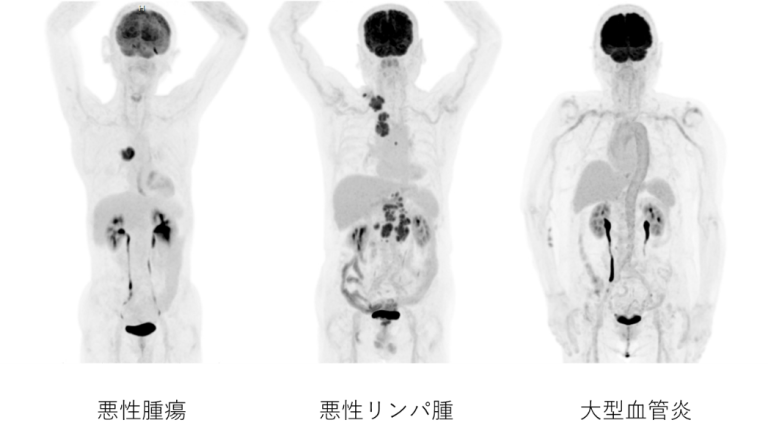

- 早期胃がんを除く、すべての悪性腫瘍、悪性リンパ腫:他の画像診断により病期診断、転移、再発診断ができない時

- 大型血管炎

PET検査症例